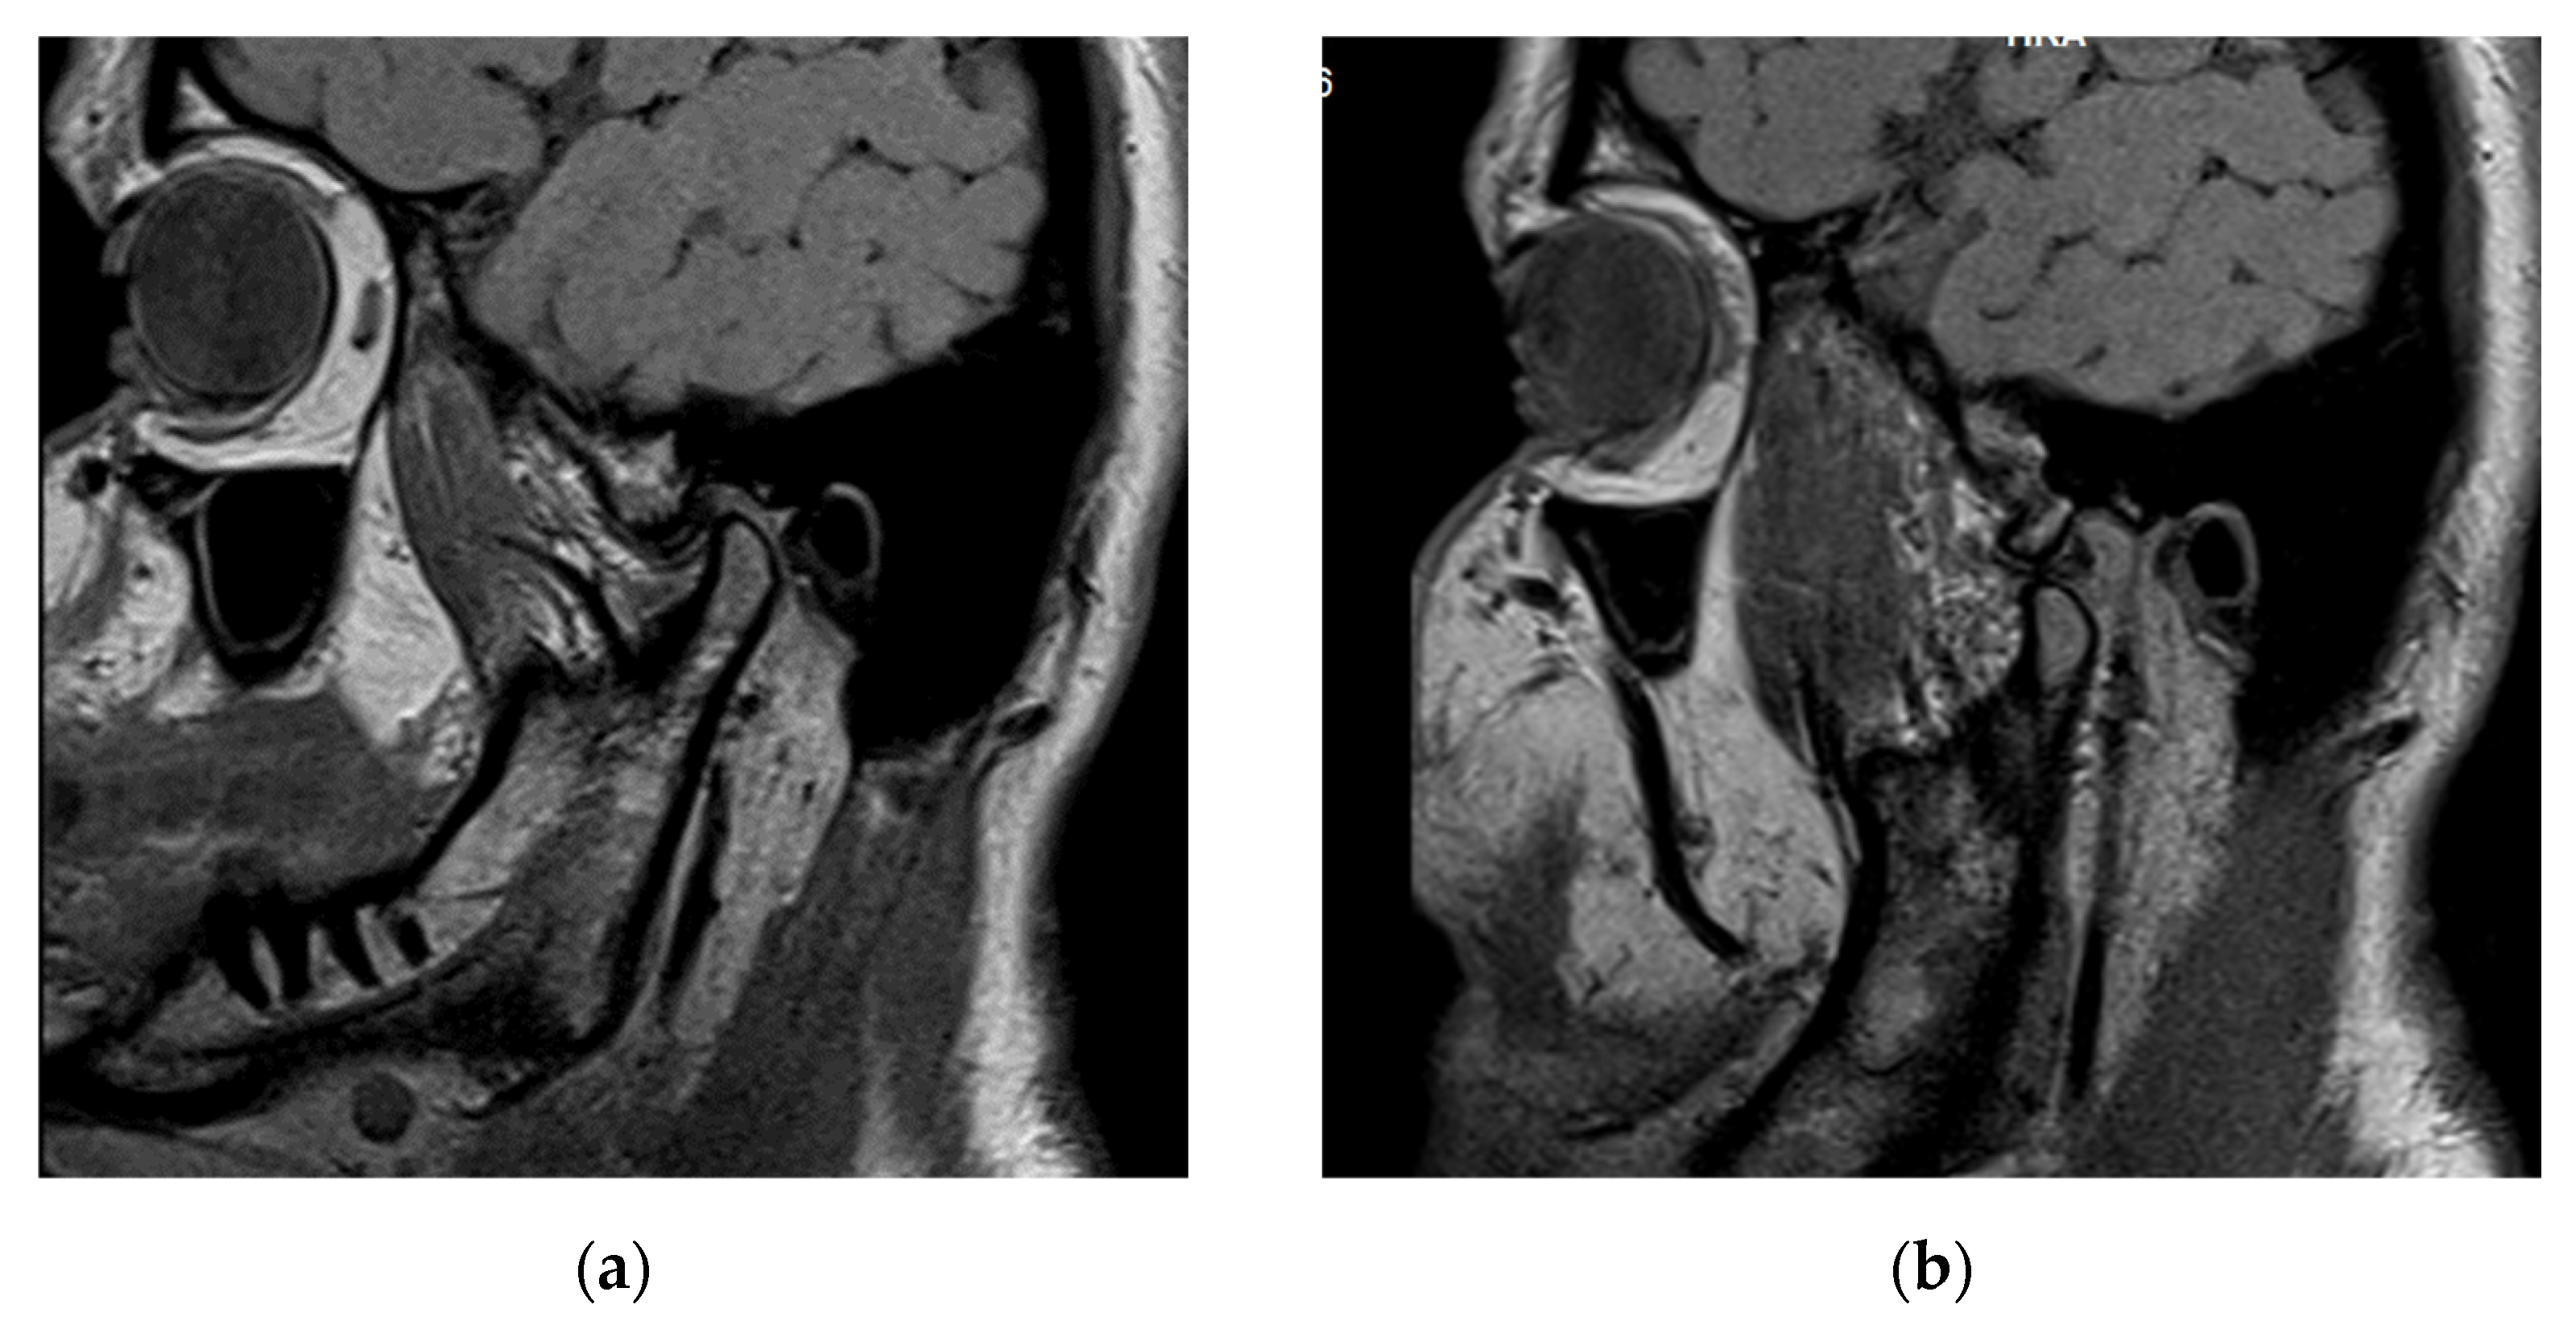

3.3. Case Report